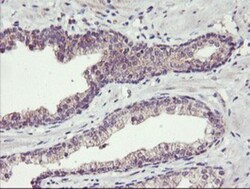

| Antigen | TMEFF2/Tomoregulin-2 |

| Applications | Western Blot, Immunohistochemistry, Immunohistochemistry (Paraffin) |

| Dilution | Western Blot 1:500-2000, Immunohistochemistry 1:150, Immunohistochemistry-Paraffin 1:150 |